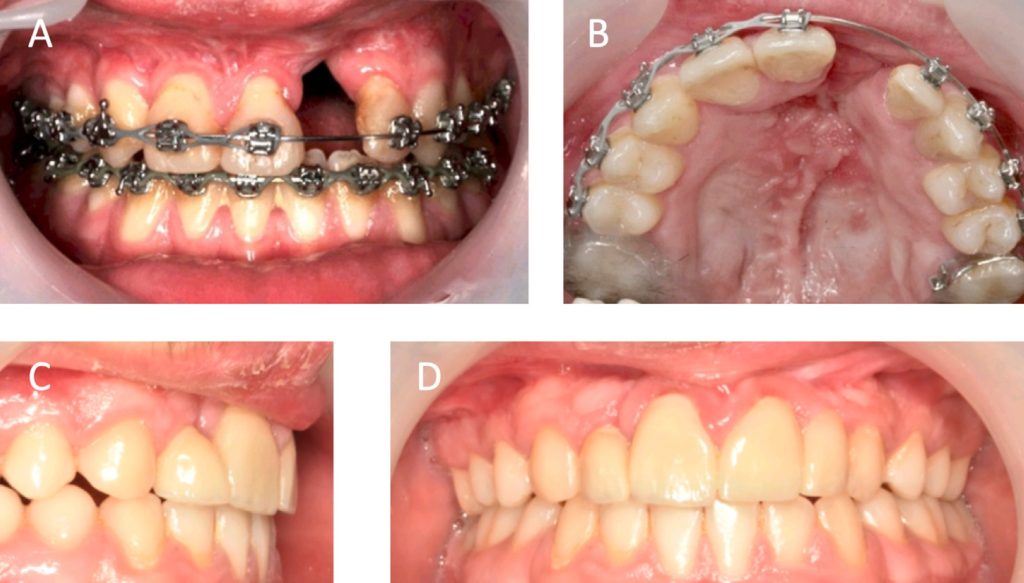

Directo del Journal of Digital Orthodontics les traemos un artículo llamado Severe Class III Malocclusion with Anterior Crossbite and Anterior Crowding: Camouflage Treatment with Premolar Extractions. Los autores nos describen el tratamiento de camuflaje de un hombre de 33 años con maloclusión Clase III esquelética severa (-4.5° ANB), apiñamiento anterior, mordida cruzada y un perfil cóncavo . Debido al rechazo del paciente a la cirugía, optaron por un enfoque ortodóntico .

El tratamiento consistió en la extracción de los segundos premolares maxilares y los primeros premolares mandibulares para generar espacio . Se utilizaron brackets de autoligado pasivos, combinados con tbite-turbos, elásticos Clase III y open coil para corregir la mordida cruzada anterior y retraer el arco mandibular.

Después de 39 meses, se logró un perfil facial y una oclusión satisfactorios . Los resultados incluyeron una mejora de 7° en la inclinación de los incisivos superiores y un mantenimiento del torque inferior, retracción mandibular de 8 mm y del labio inferior de 4 mm. ¿Como llegaron a eso? Muy fácil…